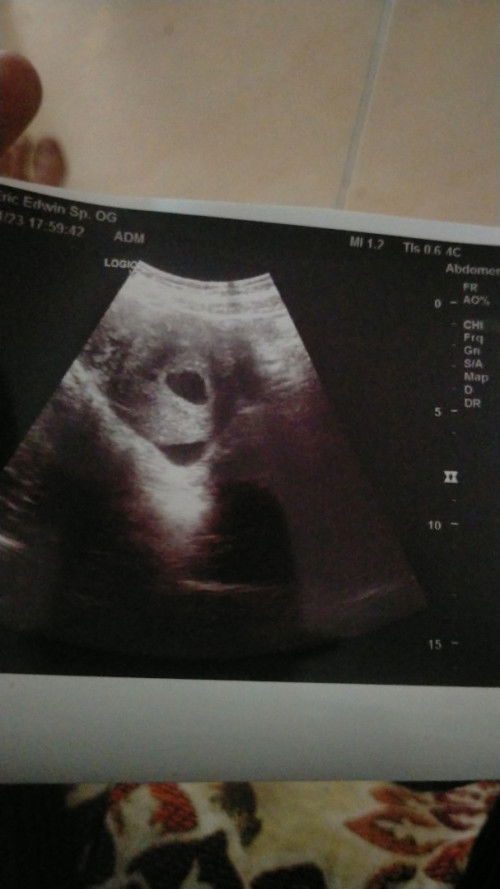

Moms mau tnya dong tadi usg Kok ada 2 kantong ya itu pertanda apakah berbahaya???

kmren aku usg 2 kli pas 5 week blum ad kntong khmilan yang ke 3 liat kntong khmiln sudah seneng bgt ..smpe g ngeh klo ad 2 kntong bun, jadi ceritanya pas aku liatin saudra malah bilang kok ad 2 kantong?aku mlh g tau tak kira emng harusny 2

yg satunya kantong urine bun